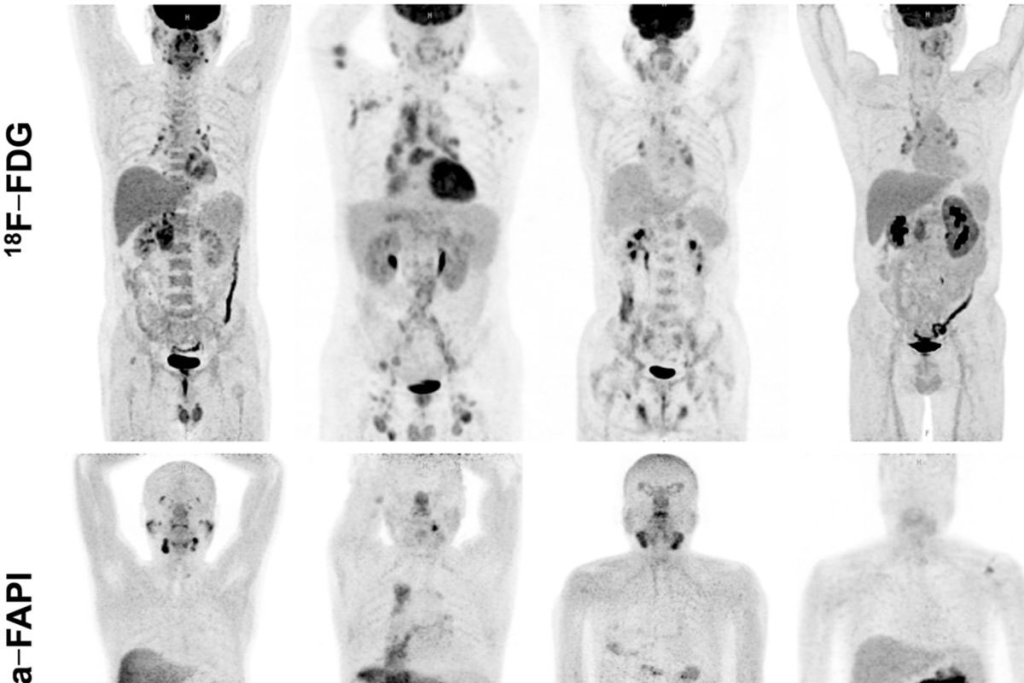

Understanding PET Scan Black Spots Meaning

Black spots on PET scans can mean different things about your health. They show up because of how cells work and the colors used in the scan. These scans help find diseases, like cancer, by showing how active cells are.

Color Interpretation in PET Imaging

PET scans use colors to show how active cells are. Bright colors mean cells are very active, often a sign of cancer. Knowing this color scale is key for correct diagnosis.

The colors range from black (low activity) to white (high activity). There are also shades of gray and other colors, depending on the tracer used.

Why Some Areas Appear Dark or Black

Dark or black spots on PET scans mean low cell activity. This can be because of:

• Normal tissue with low metabolic rate

• Benign conditions

• Certain types of cancer that don’t show high activity

Figuring out why these spots appear needs a detailed look at the scan. This is often done with other tests too.